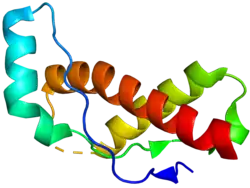

| 3D structure of major prion protein | |

Prions consist of a misfolded form of major prion protein (PrP), a protein that is a natural part of the bodies of humans and other animals. The PrP found in infectious prions has a different structure and is resistant to proteases, the enzymes in the body that can normally break down proteins. The normal form of the protein is called PrPC, while the infectious form is called PrPSc – the C refers to 'cellular' PrP, while the Sc refers to 'scrapie', the prototypic prion disease, occurring in sheep.[21] PrP can also be induced to fold into other more-or-less well-defined isoforms in vitro; although their relationships to the form(s) that are pathogenic in vivo is often unclear, high-resolution structural analyses have begun to reveal structural features that correlate with prion infectivity.[22]

PrPC

PrPC is a normal protein found on the membranes of cells, "including several blood components of which platelets constitute the largest reservoir in humans".[23] It has 209 amino acids (in humans), one disulfide bond, a molecular mass of 35–36 kDa and a mainly alpha-helical structure.[24][25] Several topological forms exist; one cell surface form that is anchored via glycolipid, and two transmembrane forms.[26] The normal protein is not sedimentable; meaning that it cannot be separated by centrifuging techniques.[27] It has a complex function, which continues to be investigated. PrPC binds copper(II) ions (those in a +2 oxidation state) with high affinity.[28] This property is supposed to play a role in PrPC’s anti-oxidative properties via reversible oxidation of the N-terminal’s methionine residues into sulfoxide.[29] Moreover, studies have suggested that, in vivo, due to PrPC’s low selectivity to metallic substrates, the protein’s anti oxidative function is impaired when in contact with metals other than copper.[30] PrPC is readily digested by proteinase K and can be liberated from the cell surface by the enzyme phosphoinositide phospholipase C (PI-PLC), which cleaves the glycophosphatidylinositol (GPI) glycolipid anchor.[31] PrP plays an important role in cell-cell adhesion and intracellular signaling in vivo,[32] and may therefore be involved in cell-cell communication in the brain.[33]